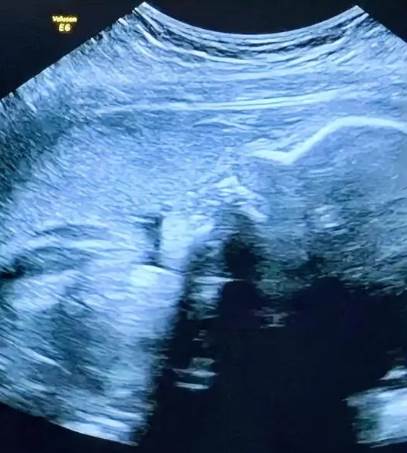

其實醫生早該告訴她:四維彩超里蜷縮的小腳只有葡萄大,握拳的樣子像在說「媽媽我來了」。那些執著了半輩子的「男女」,在孩子第一次睜眼望向你時,突然就變得不重要了。孩子健康才是寶,珍惜這份緣!對兒女有分別心,是心的問題,其實兒女都是你的種。